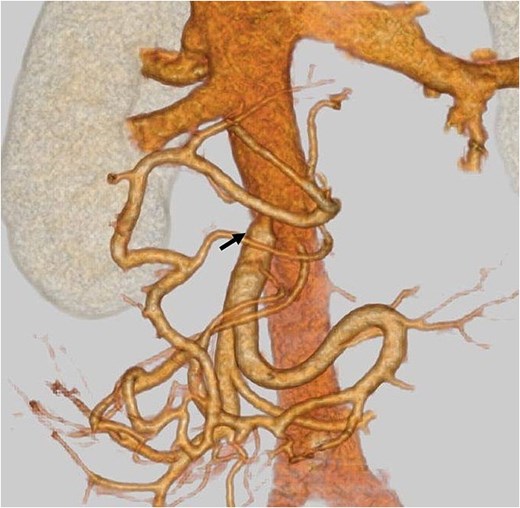

A mesenteric approach was first undertaken, and both the SMV and SMA were encircled at the root of the small bowel mesentery. After pancreatic transection, the hemicircumferential nerve plexus dissection of the SMA was performed (Fig. 2, left). Following encirclement proximal to its confluence with the SPV, the SMV was transected using an Endo GIA™ stapler and resected en bloc during a classic Whipple procedure. Although no congestion was observed during test clamping of the stenotic SMV, significant jejunal congestion was noted after resection. There was a considerable gap of ⁓12 cm between the stump of the proximal JV and the PV (Fig. 2, right), such that a VG from the neck alone could not reach. As a result, a shunt was created between a jejunal branch of the SMV and the inferior vena cava (IVC) (Fig. 3). Reconstruction was performed using a modified Child procedure. The transverse colon was resected up to the splenic flexure, and ileocolic re-anastomosis was conducted at a well-perfused site (Fig. 3). Operative time was 463 min and estimated blood loss was 400 cc.

(a) Intraoperative photographs: Hemicircumferential dissection of the SMA nerve plexus, followed by en bloc SMV resection. (b) The SMV was transected proximal to its junction with the splenic vein. The SMA and SMV are encircled with vessel loops. The photograph illustrates the considerable gap between the SMV transection site and the jejunal branch stump (double-headed arrow). SMA: Superior mesenteric artery, SMV: Superior mesenteric vein.